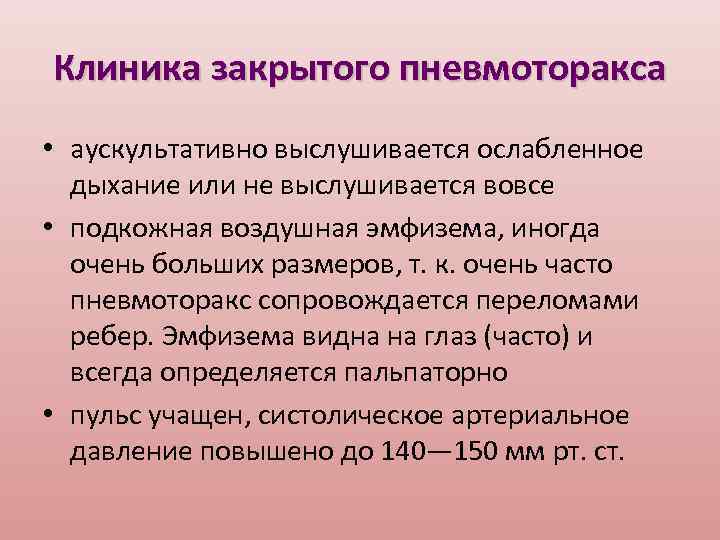

Схемы дыхания: Пневмоторакс на изображениях